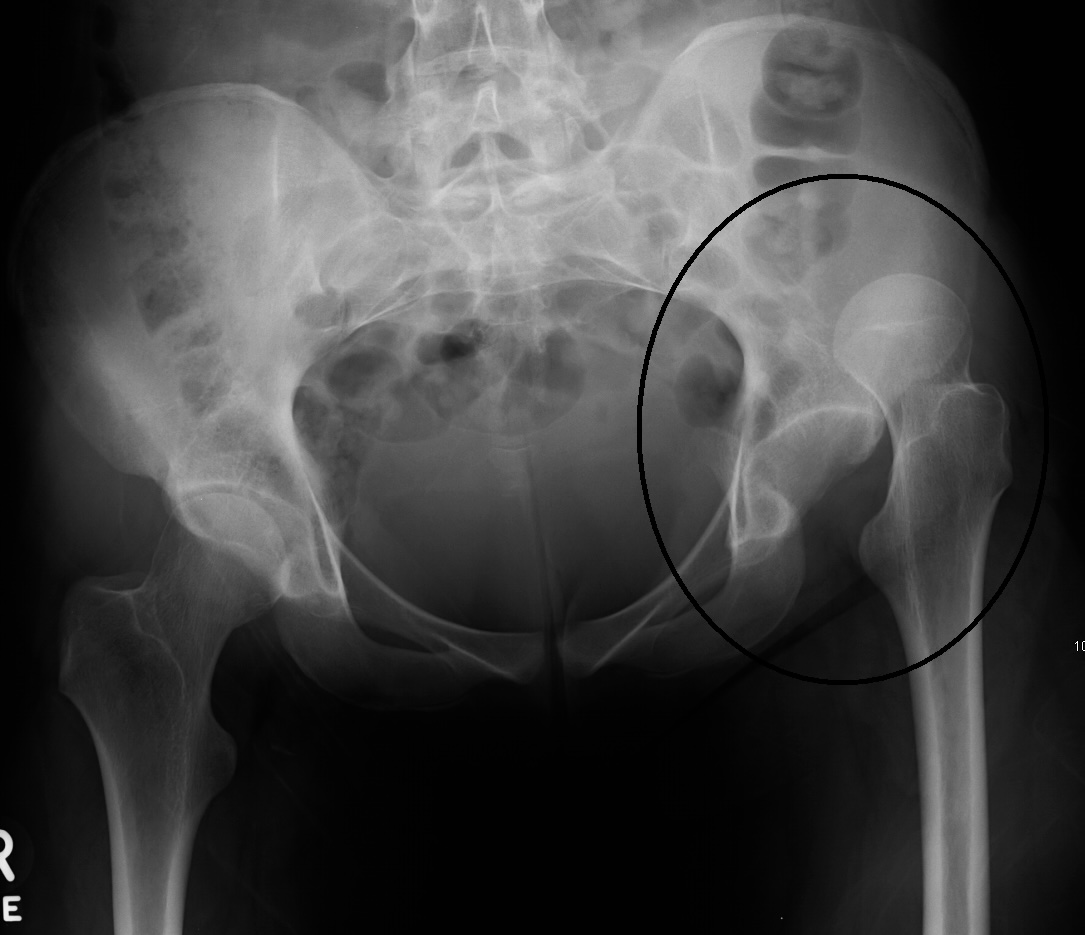

Привычный вывих бедра:

Смещение головки бедренной кости кпереди или кзади за пределы вертлужной впадины, иногда с частичным сохранением контакта.

Плоскость вертлужной впадины уплощена или деформирована, часто имеются краевые костные разрастания.

Расширение суставной щели, расхождение оси головки и впадины.

Признаки дисплазии: гипоплазия крыши вертлужной впадины, увеличение её наклона, недоразвитие заднего края.

Деформация головки бедренной кости, участки остеосклероза и субхондральных кист.